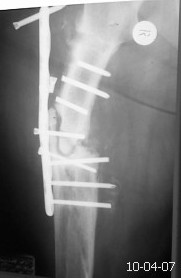

ложный сустав бедра

Ортопедия и травматология Отправлено Константин Никитин 08 Апрель 2010, 13:44

Уважаемые коллеги. Просьба помочь с тактикой лечения данной пациентки.

Травма в 2007 г. лечили больную консервативно. В 2009 г. у нас остеосинтез пластиной в сочетании с костной аутопластикой. Со слов больной после операции, дома в течение 6-ти месяцев соблюдала постельный режим,после чего начала ходить.Больная повышенного питания, сахарный диабет 2-го типа, неопрятна.Фотографию прилагаю. Планируем выполнить реостеосинтез пластиной с угловой стабильностью с повторной аутопластикой и пластикой по Хахутову.У кого какие мнения по поводу лечения?С уважением Никитин Константин

С учетом диабета однозначно оптимальный способ фиксации это закрытый БИОС, удаление м/конструкции малоинвазивный (вариант А.Н.) тем более гипертрофический ложный сустав (судя по снимку) в динамической версии БИОС должна сростись. Удачи.